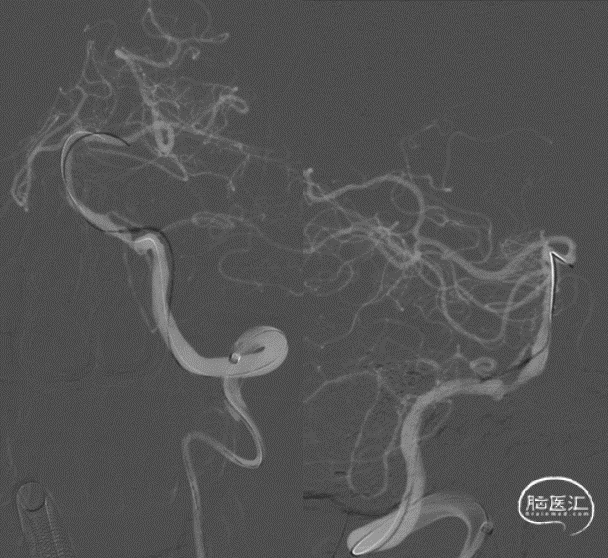

复查DSA:左侧椎动脉V4段重度狭窄。

病变部位:左侧椎动脉V4段

远端正常血管直径(mm):3.6

狭窄处最小直径(mm):0.55

病变长度(mm):8.15

狭窄度(%):84.72%

术后影像及检查

术中DynaCT。